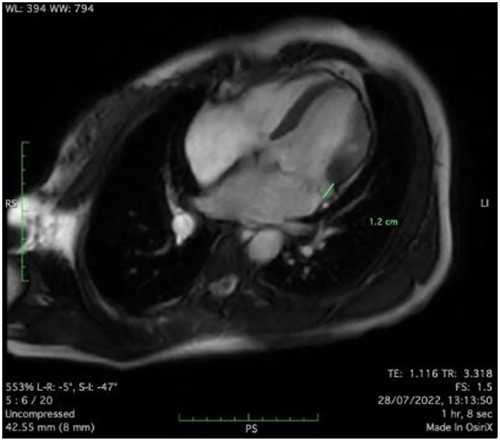

Clinically, both patients complained of worsening palpitations over the last few months with no associated dyspnea or tiredness. A Holter examination recorded 14 444 VES and 212 NSVT, with very similar results in both sisters. The echocardiography revealed a myxomatous Barlow mitral valve with anterior and posterior leaflet prolapse and two regurgitant jets resulting in moderate to severe mitral valve regurgitation as well as mitral annular disjunction in both cases (Figs 1 and 2). A cardiac MRI on a 3 T Lumina Siemens revealed at the mid-left ventricular level, a midwall fibrosis in the midlateral myocardium (Figs 3 and 4) and confirmed a mitral annular disjunction of 12 mm (Figs 5 and 6). Additional findings included a dilated LV with mildly depressed contractility, no visible myocardial scarring, no structural heart disease and a normal sized RV with mildly depressed contractility.